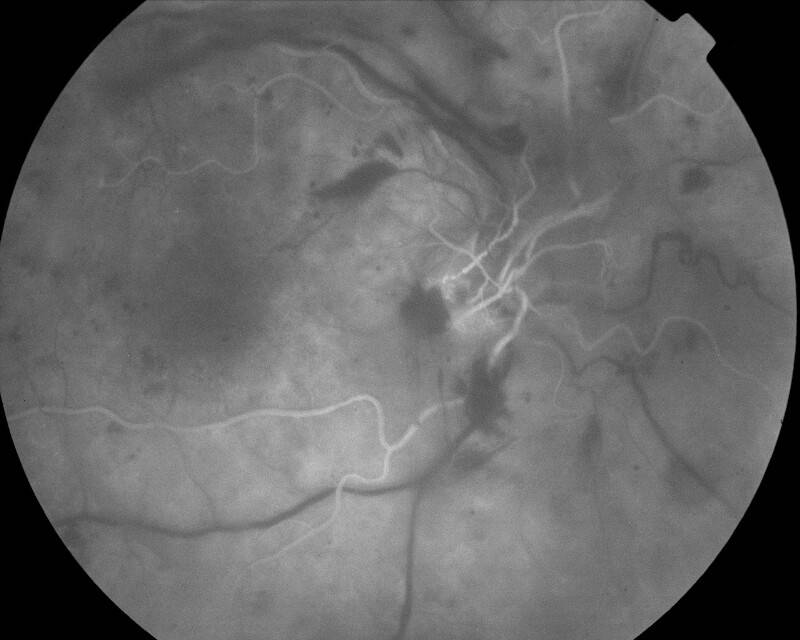

RETINOPATHIE DIABETIQUE PROLIFERANTE